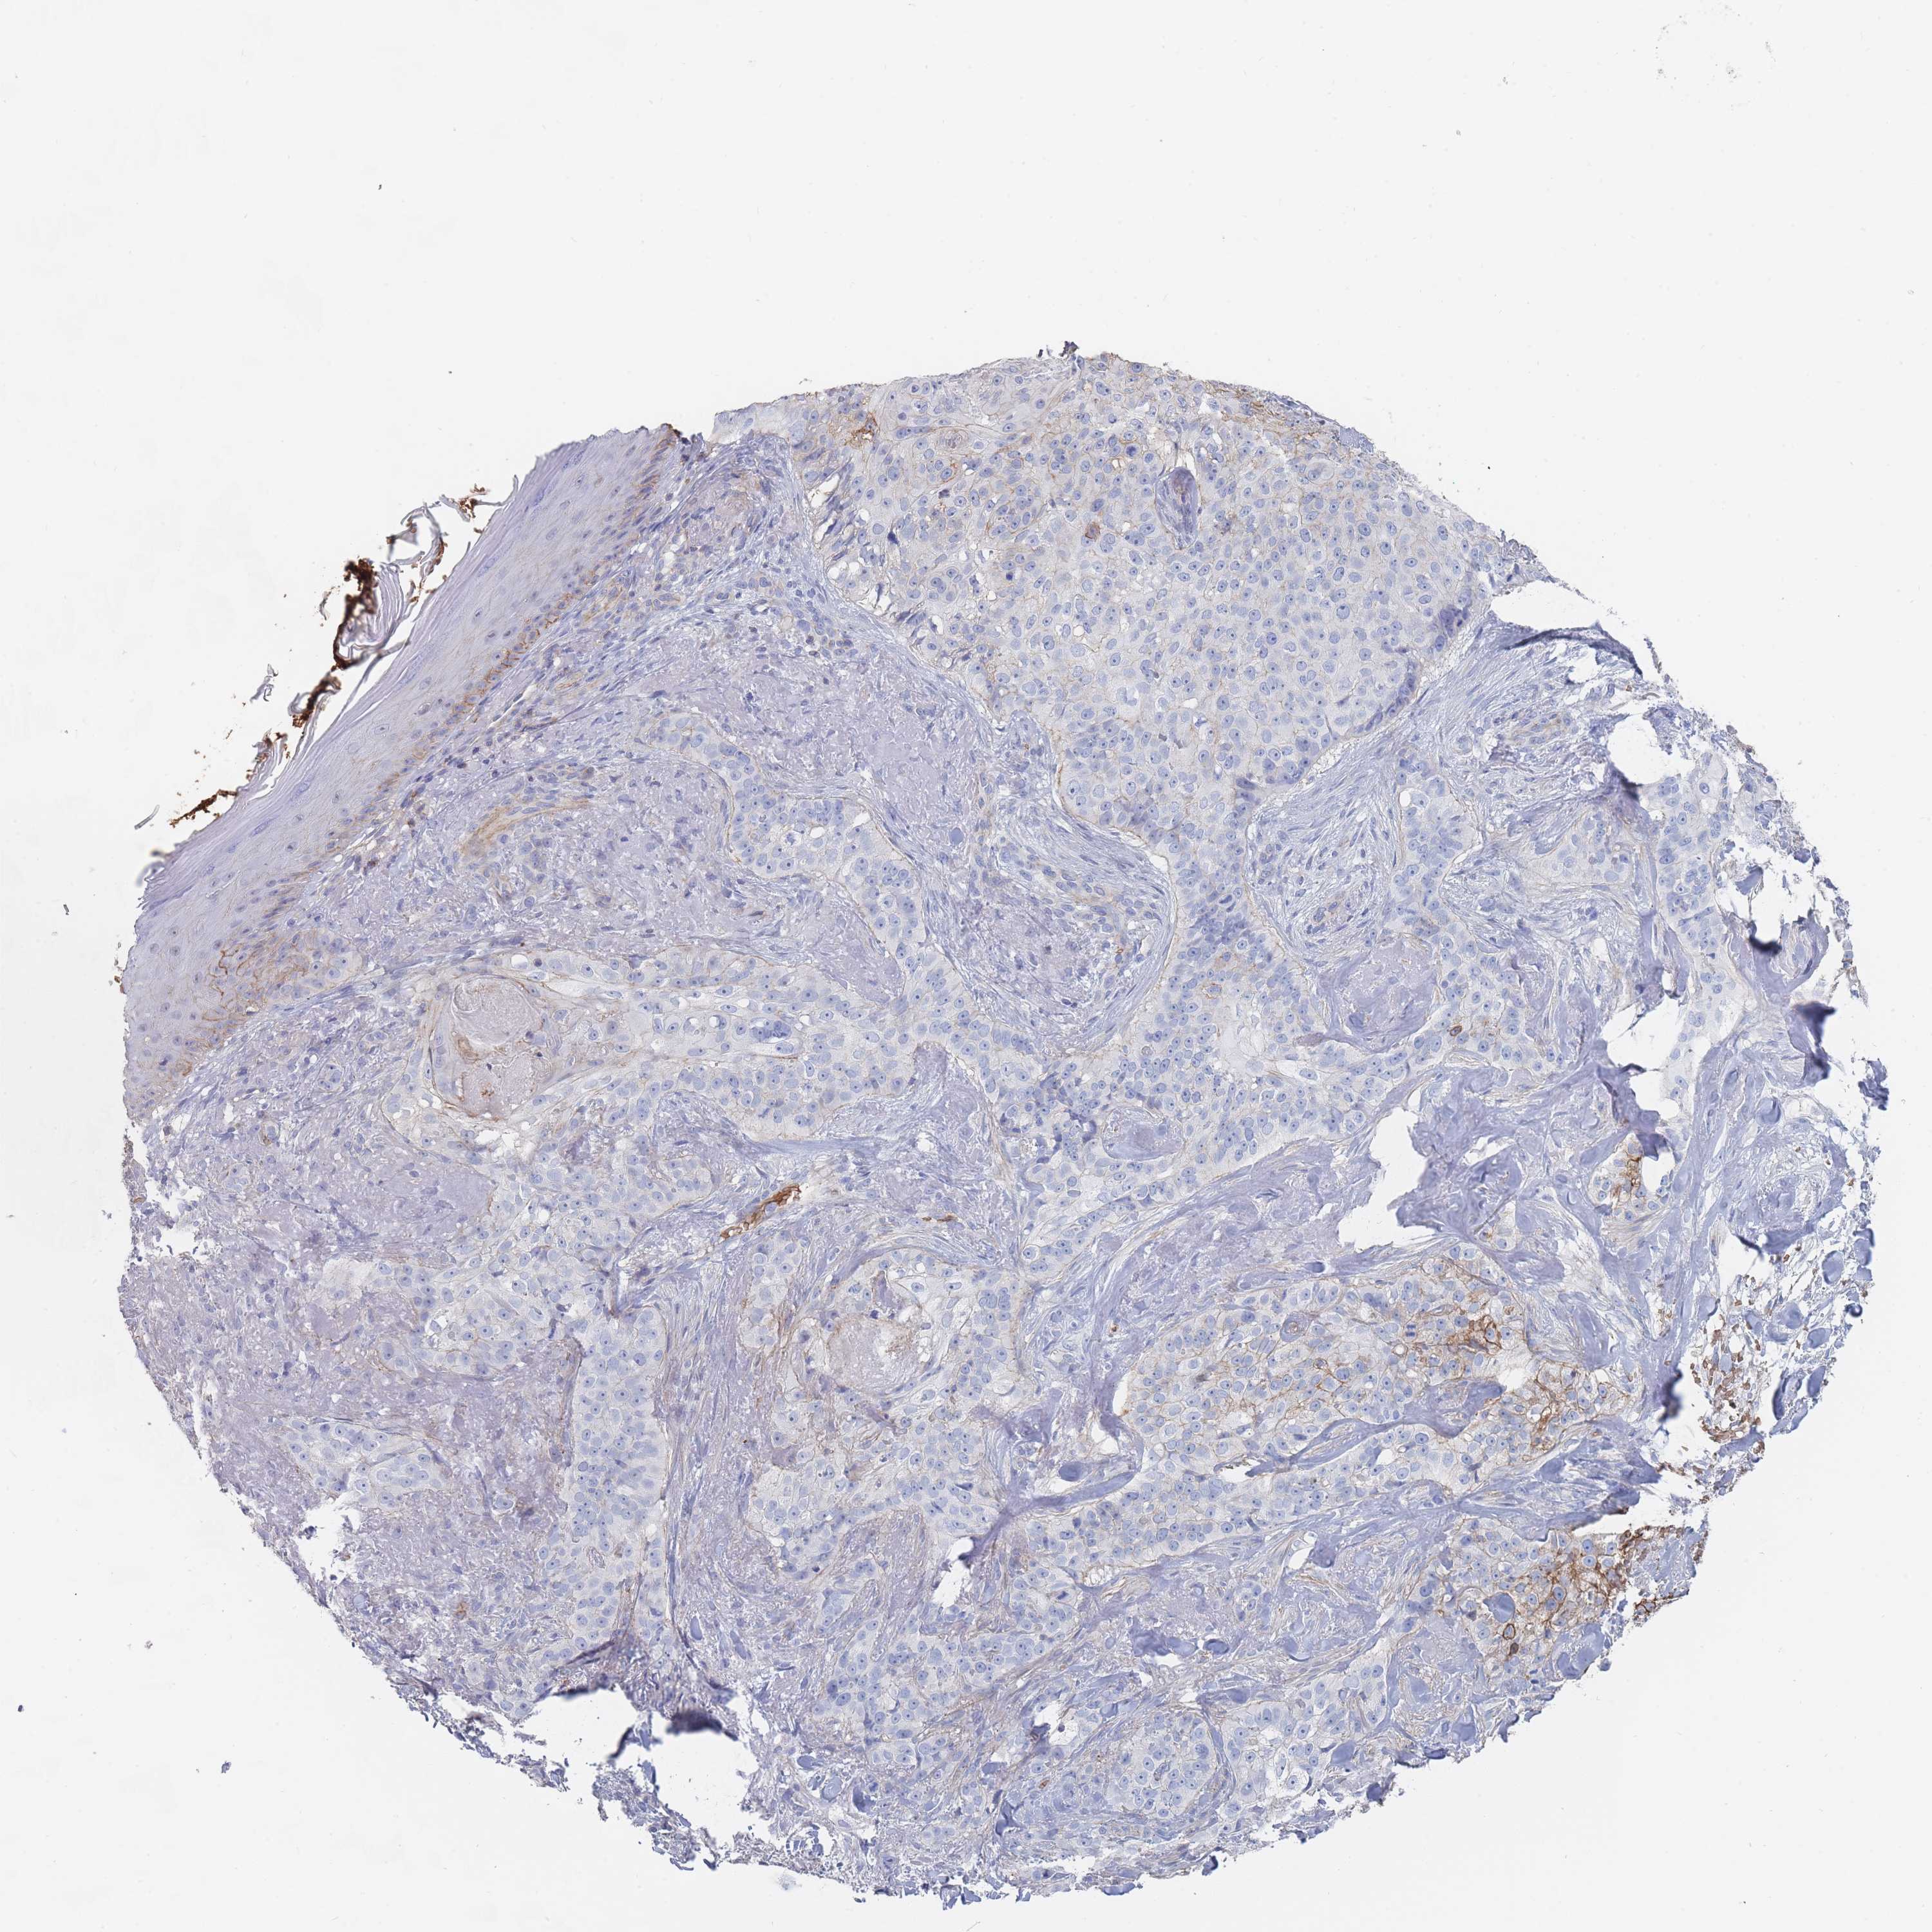

Basal cell and squamous cell cancer

SKIN CANCER - Protein expressioni

A mouse-over function shows sample information and annotation data. Click on an image to view it in a full screen mode. Samples can be filtered based on level of antibody staining by selecting one or several of the following categories: high, medium, low and not detected. The assay and annotation is described here.

Each image is clickable and will lead to virtual microscopy that enables deeper exploration of all samples and also displays staining intensity scores, fraction scores and subcellular localization as well as patient and tissue information for each sample.

Antibody HPA031345

Basal cell carcinoma